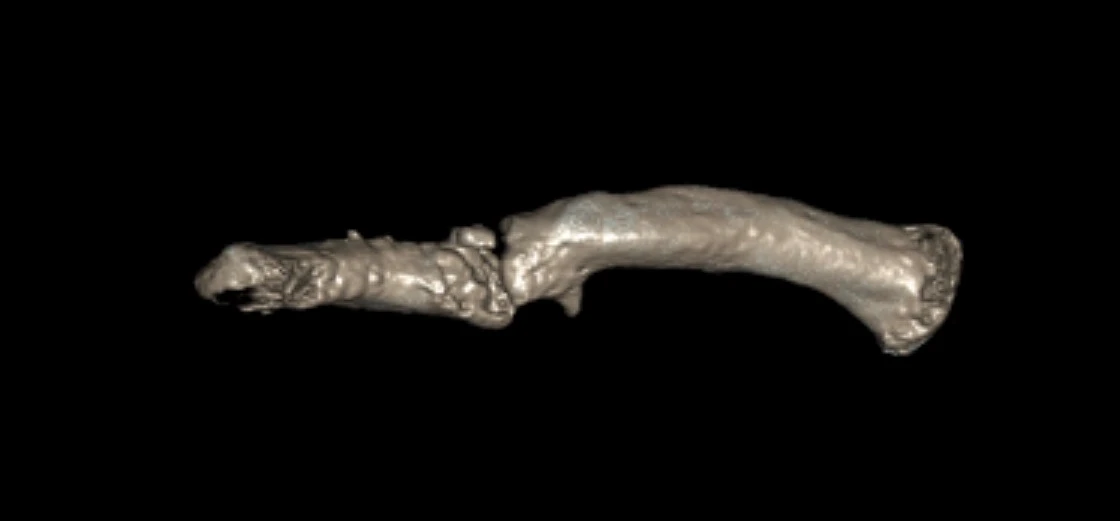

Subsequent imaging confirmed an established hypertrophic non-union of the right clavicle. CT scans and preoperative planning were arranged to assess the feasibility of surgical correction with bone grafting to restore clavicular length. A careful plan was put forward to possibly take down his nonunion, bone graft the defect and replate the clavicle.

This was all done with 3D CT imaging.

Pre op 3D model 1 clavicle nonunion

Pre op 3D model 1

Pre op 3D model 2 clavicle nonunion

Pre op 3D model 2